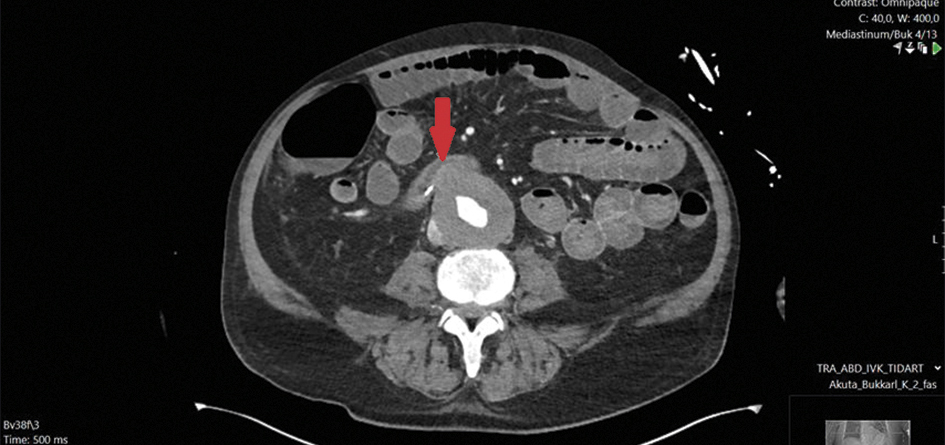

Fallbeskrivning Ovanlig genes till livshotande gastrointestinal blödning